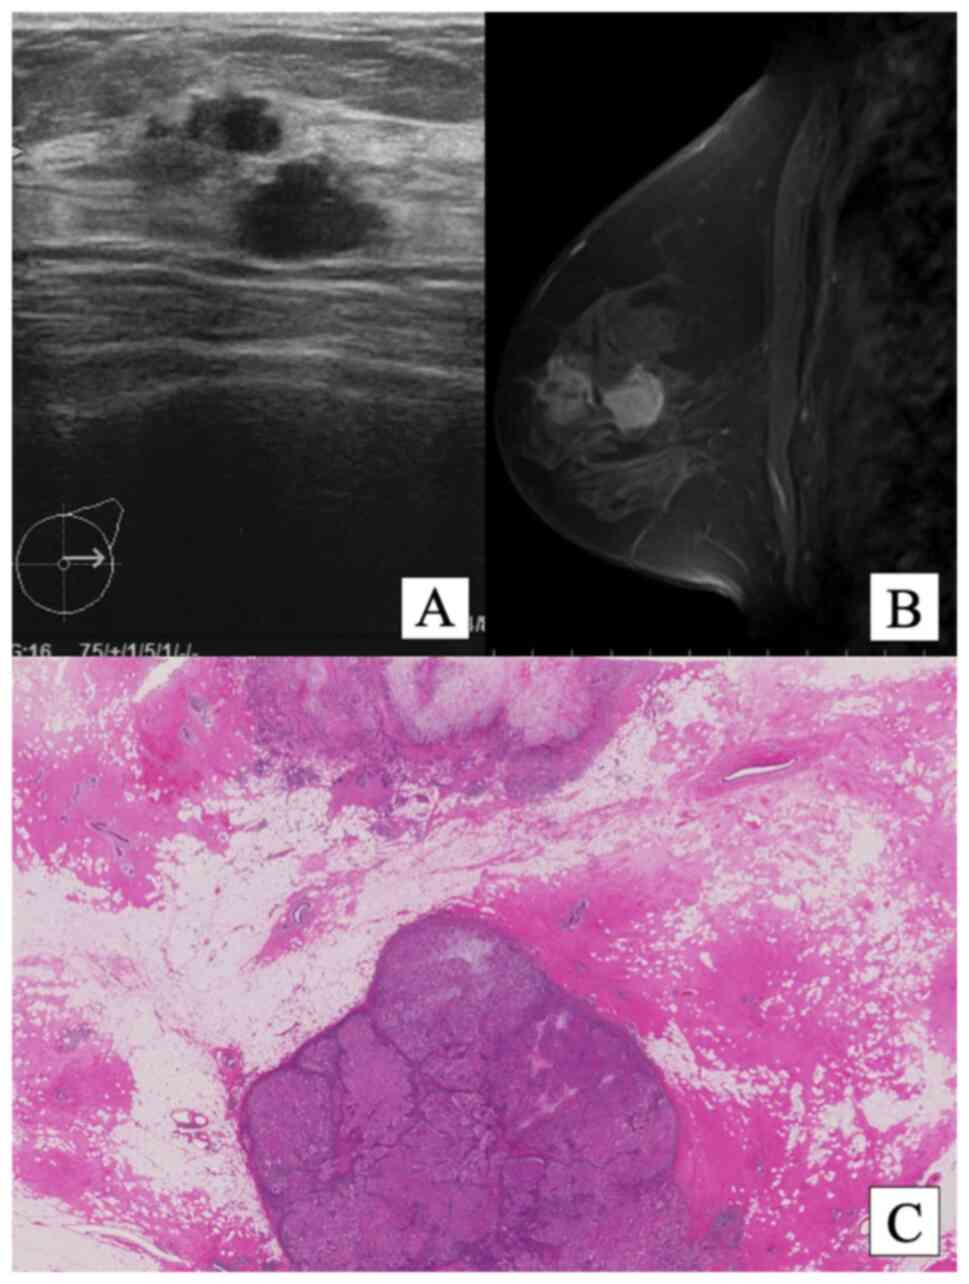

Metaplastic breast carcinoma producing prominent basal lamina with neuroendocrine differentiation: A case report

Metaplastic breast carcinoma (MBC) is a heterogeneous group of invasive breast carcinomas (IBCs) characterized by the differentiation of the neoplastic epithelium toward squamous cells and/or mesenchymal‑appearing elements. The present study describes the case of a 42‑year‑old woman who underwent a mastectomy and sentinel lymph node biopsy for two tumors in their left breast. One of the resected tumors was diagnosed as MBC with neuroendocrine (NE) differentiation and the other was diagnosed as IBC of no special type. The MBC tumor contained a matrix composed of basal lamina with a focal area of myxoid matrix and squamoid differentiation. To the best of our knowledge, the present study is the first report of MBC producing prominent basal lamina. The patient has remained alive and well for >10 years without recurrence, and has been treated with oral and injected anticancer drugs.

Figure 1